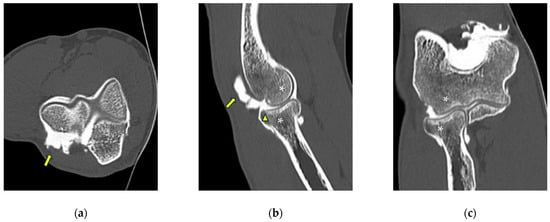

Figure 6.

CT-arthrography of a professional motocross rider with chronic elbow pain due to repeated microtraumatism. (a,b) Axial and sagittal images show pathological widening of the postero-lateral recess (yellow arrows); (b,c) sagittal and coronal images show articular asymmetry of the humero-radial joint (asterisks), diffuse cartilage fraying and a full-thickness chondral defect (grade IV) of the posterior aspect of the radial head dish (yellow arrowhead).